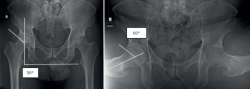

Se trata de un paciente masculino de 45 años, sin antecedentes clínicos de importancia. Acude por dolor en la cadera derecha sin causa, que incrementa con la actividad física, la bipedestación y la sedestación prolongada. A la valoración presenta flexión de 120° dolorosa, extensión de 30°, abducción de 40° dolorosa, aducción de 30°, rotación interna de 15° dolorosa y rotación externa de 25° dolorosa; maniobras: FABER +, FADIR + y log roll +; escala funcional médica Hip Outcome Score (HOS) de 35/68 (51,5%) puntos y escala visual analógica (EVA) del dolor de 7/10. En la radiografía anteroposterior de pelvis y en posición de Dunn a 90° se evidencia esclerosis de la cabeza femoral, además de morfología de tipo cam y pincer (Figura 1). En la artrorresonancia magnética de la cadera derecha, se evidencia una imagen hipointensa en la secuencia T2, con bordes hiperintensos en la secuencia T1 (signo de doble contorno), desgarro del labrum acetabular de Czerny-Hoffman(8) IIIA, adelgazamiento de cartílago articular, sin colapso de la cabeza femoral. El ángulo de Kerboul(9) medido es de 284° con alto riesgo de colapso de la cabeza femoral (Figura 2).

Figura 1. Radiografía anteroposterior (AP) de pelvis y proyección de Dunn a 90°, evidenciando un ángulo centro borde (Wiberg) aumentado de 50° y un ángulo alfa aumentado de 60°.